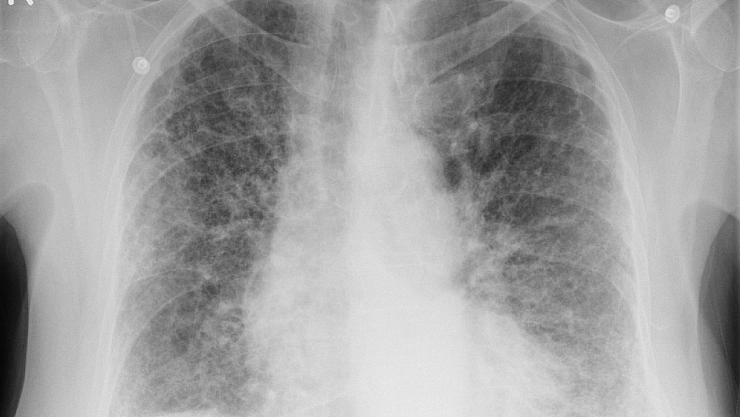

Pulmoner fibroz, yani akciğer fibrozu geliştiğinde, akciğerlerin iç yüzeyini kaplayan hava kesecikleri ve akciğer dokusunun destekleyici yapıları zarar görüyor. Akciğerin bu yapılarının kalınlaşıp sertleşerek esnekliğini kaybetmeleri, içimize solunumla çektiğimiz oksijenin kanımıza geçişine engel oluyor. Bunun sonucunda nefes darlığı gelişmeye başlıyor ve ilerleyince solunum yetmezliğine neden olabiliyor. Dünyada tanı konulan 1-1,5 milyon pulmoner fibroz hastası olduğu belirtiliyor. Ancak tanı konulmamış hastalar da düşünüldüğünde gerçek rakamın daha yüksek olduğu tahmin ediliyor. Türk Toraks Derneği’nin yaptığı araştırmaya göre; ülkemizde her yıl yaklaşık 4 bin kişiye pulmoner fibroz tanısı konuluyor.

Pulmoner fibroza neden olabilen pek çok etken var. Bağdokusu hastalıkları (romatoid artrit, skleroderma gibi), çeşitli kimyasal gazlar gibi mesleksel veya çevresel maruziyetler ya da bazı ilaçlar bu hastalığa en sık yol açan nedenler. Pulmoner fibroza sebep olabilecek bir etken bulunamazsa “idyopatik pulmoner fibroz” olarak adlandırılıyor. Bilgisayarlı tomografi, solunum fonksiyon testleri, bronkoskopi ile akciğerden alınan yıkantı sıvısı veya biyopsi ile nadiren cerrahi akciğer biyopsisi de hastalığın teşhisinde kullanılan en önemli araçları oluşturuyor.